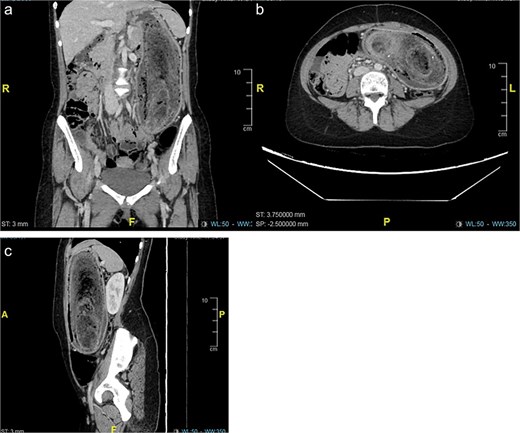

Baseline laboratory tests were within normal limits. A computed tomography (CT) scan of the abdomen confirmed the presence of a sizable bezoar extending from the stomach into the duodenum, consistent with gastric outlet obstruction (Fig. 1). Diagnostic upper gastrointestinal endoscopy revealed a large mass of hair occupying the stomach and extending beyond the pylorus (Fig. 2).

(a–c) Computed tomography (CT) revealed a distended stomach with large endoluminal mass of heterogeneous material likely representing trichobezoar. Mucosal hyper-enhancement of the stomach.